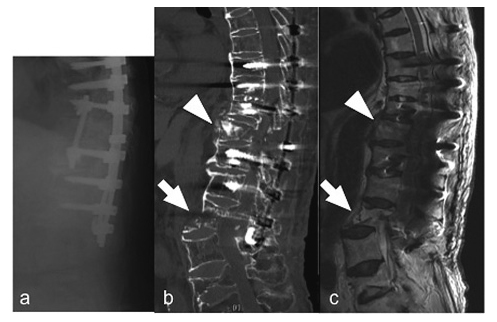

An 86-year-old woman with no significant past medical history presented with acute back pain after a fall and was transferred to her local hospital. Plain radiographs showed a bone bridge spanning more than four intervertebral bodies without a narrow intervertebral space (Figure 1a, b). Magnetic resonance imaging (MRI) showed a Th10 fracture (Figure 1c). She was diagnosed as having DISH and a Th10 fracture. She underwent conservative treatment because of her extreme age and no clear instability. She started gait exercise at 2 weeks after injury with immobilization by a rigid orthosis. Twenty-five days after injury, she presented with bilateral leg paralysis and numbness. Since delayed paraplegia was suspected, she was transferred to our hospital for surgical treatment. On admission, she had bilateral leg paralysis (grade 3 on manual muscle testing: MMT) below the iliopsoas and hypoesthesia of the anterior thighs. She had no bladder or bowel dysfunction. A lateral plain radiograph showed a decreased local kyphotic angle (Figure 2a). Computed tomography (CT) showed anterior expansion with a bone defect in the Th10 vertebral body and subsequent decreased kyphosis due to distraction-extension injury (reverse Chance fracture) (Figure 2b) and ossification of the ligamentum flavum at bilateral T10/11. MRI showed an intramedullary high-intensity area on T2-weighted images (Figure 2c), indicating instability and non-union at the same level. She underwent surgery 50 days after the injury. Laminectomy of Th10, partial laminotomy of Th11, Th7-L1 posterior fusion with pedicle screws and additional stabilization with laminar hooks to Th6 and L1 laminae to avoid back out of the screws, Th9-11 anterior fusion with a plate, and autologous bone grafting were performed simultaneously (Figure 3). In situ fusion in the prone position was done with no alignment correction. After surgery, her paralysis improved, and she started gait exercise with no limitation. Eight days after surgery, she presented with low back pain and paralysis (grade 2 on MMT) in her legs with no apparent cause. CT revealed an L1 fracture in the middle of the vertebral body, which was the caudal end of the fusion (Figure 4b). The patient refused further surgical treatment and werewas transferred back to the previousinitial hospital. She was bedridden thereafter because of the pain, and theher paralysis did not improve. Finally, shethe patient was die of pneumonia 4 month after surgery.

Lateral plain radiograph (a), CT (b), and MRI (c) immediately after the postoperative L1 fracture showing the L1 vertebral fracture in the middle of the L1 vertebral body (arrow) and dorsal displacement at the L1 level. No alignment change is observed at the Th10 level (arrowhead).

The present case showed a fracture at the caudal end of the fusion in the early stage after surgery. To date, no cases involving postoperative fractures after fusion for vertebral fractures with DISH have been reported. Inappropriate postoperative alignment may have been the reason for this fracture. It has been reported that patients with DISH have rigidity of the spine and kyphotic change15). Thus, the ability of spinal alignment to change and compensate would have been poor in this patient. The local kyphotic angle was 2° at the initial visit; however, when delayed paraplegia occurred, the angle was decreased to -8°. Finally, it was not corrected surgically, and it decreased to -11° (Figure 3). The decreased kyphosis could have caused a subsequent horizontal shear force to L1 when the patient sat on the bed and when she walked.